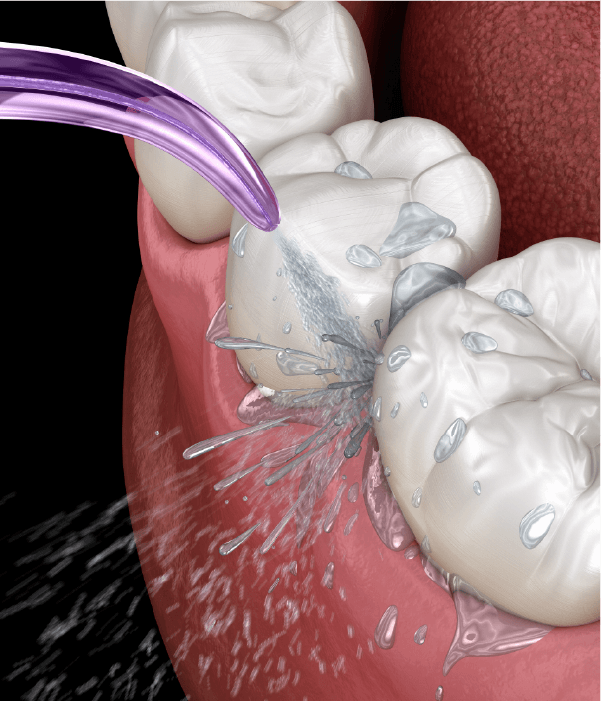

歯石がたまり、細菌が歯肉に繁殖し歯茎を悪化していく恐ろしい病気です。全身疾患と関連が深く、定期的な口腔ケアが必要です。当院では専門的な歯周病治療を行い、全身疾患から守ります。

歯周組織の腫れや炎症を診断し、口腔内の常在細菌のバランスを保つことで、むし歯や歯周病になりにくい口腔環境になります。歯周組織を健康な状態に維持し、歯の疾患から守るように専門的な治療を行います。

口腔清掃:歯石を除去する

歯周病治療:歯周組織をキレイにする

PMTC:口腔内の健康を維持する